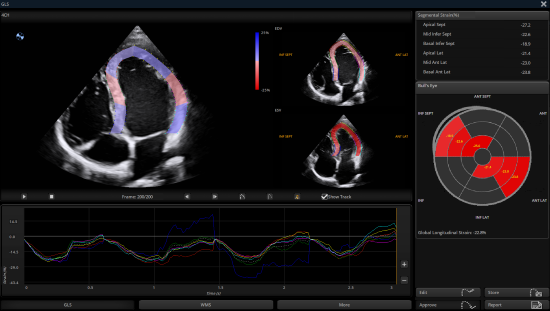

Auto SG empowers objective evaluation of LV systolic function and myocardial deformation through quantitative results in a bull’s-eye plot.